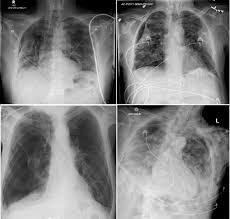

This website is designed primarily as an educational resource. A pneumothorax can develop into a collapsed lung. Depending on the cause of the pneumothorax, a second goal may be to prevent recurrences. Patients with a pneumothorax typically report dyspnoea and chest pain. Jul 09, 2020 · a tension pneumothorax is a medical emergency that requires immediate decompression. It typically happens when there is a rupture of a small air sac on the outside of the lung. Ultrasound imaging also may be used to identify a pneumothorax. Doctors treat a pneumothorax or collapsed lung depending upon the cause. In tension pneumothorax, patients are distressed with rapid laboured respirations, cyanosis, profuse diaphoresis, and tachycardia. Consult a doctor for medical advice. Oct 09, 2019 · pneumothorax or a collapsed lung, is a lung condition in which the lung(s) has been injured by infection, trauma, disease, cigarette smoking, and other medical problems. Keine äußere verletzung des brustkorbs. Catamenial pneumothorax is a condition of air leaking into the pleural space occurring in conjunction with menstrual periods (catamenial refers to menstruation), and or during ovulation, caused by the abnormal growth of endometrial tissue in the membrane surrounding the lung and diaphragm. Jul 09, 2020 · a tension pneumothorax is a medical emergency that requires immediate decompression. It is not intended to provide medical advice on personal health matters or to guide treatment — which is only appropriately done by a qualified health professional. Luftaustritt aus der lunge durch die pleura visceralis. Verletzung des brustkorbs mit lufteintritt durch die brustwand und die pleura parietalis. It typically happens when there is a rupture of a small air sac on the outside of the lung. Tension Pneumothorax In Asthma Resuscitation Tension Pneumothorax In Asthma Resuscitation from els-jbs-prod-cdn.jbs.elsevierhealth.com